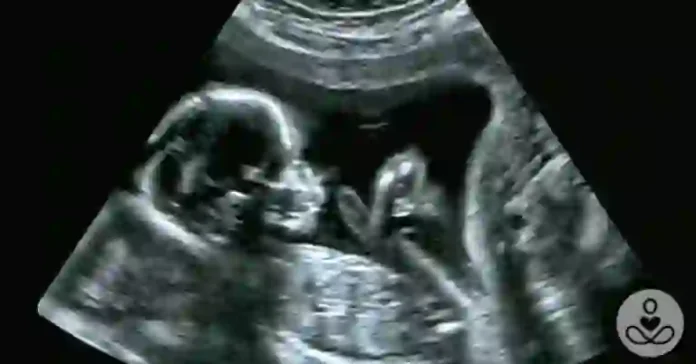

When the IL-17a molecule was artificially blocked (preventing IL-17a-induced inflammatory responses), the pups from both sets of mice were born with neuro-typical behaviors. Yet, when everything was left to progress without additional human intervention, the pups born from mothers in the first group went on to develop an autism-like neurodevelopmental condition, which affected social and repetitive behaviors.